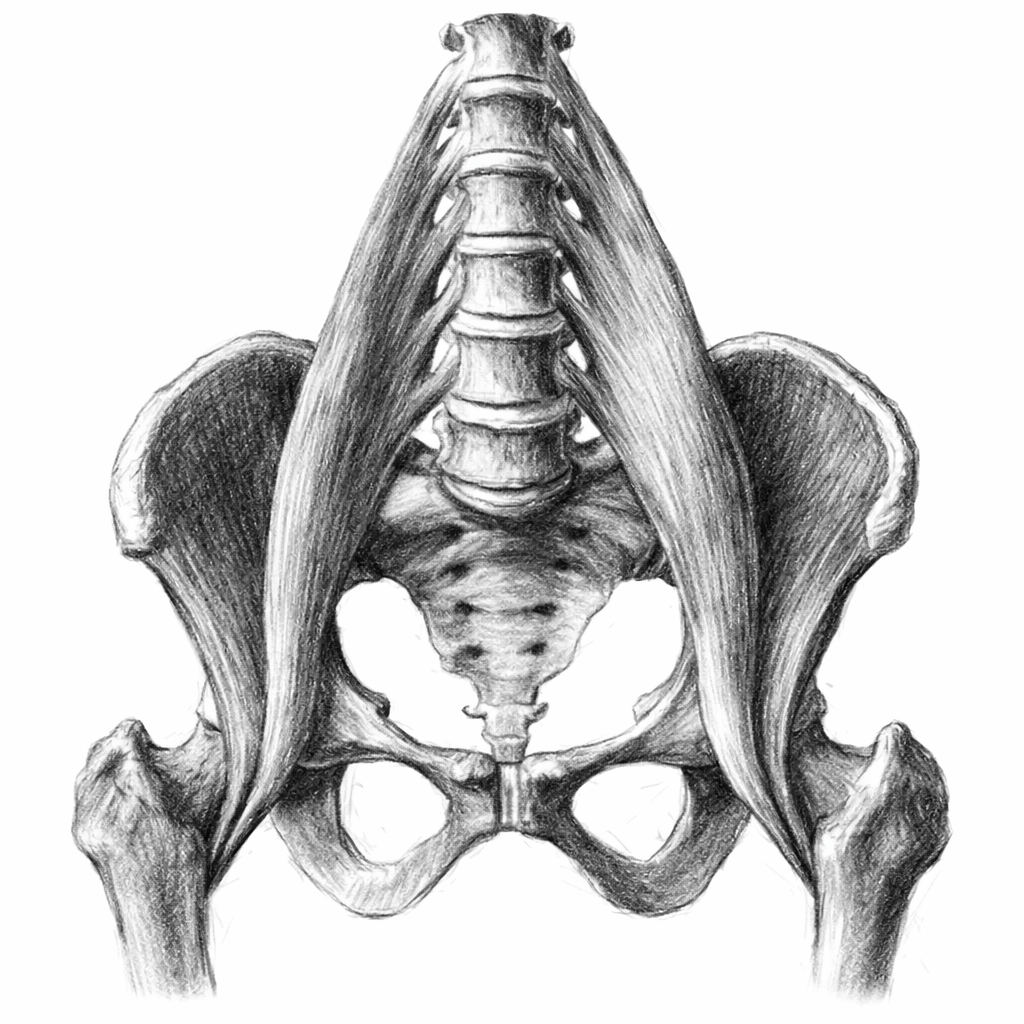

Revisión Anatómica clave (y muy breve?:

El psoas ilíaco es el principal flexor de la cadera y un músculo profundo, lo que condiciona su exploración ecográfica.

La ventana más útil suele encontrarse a nivel de la región inguinal y la cabeza femoral.